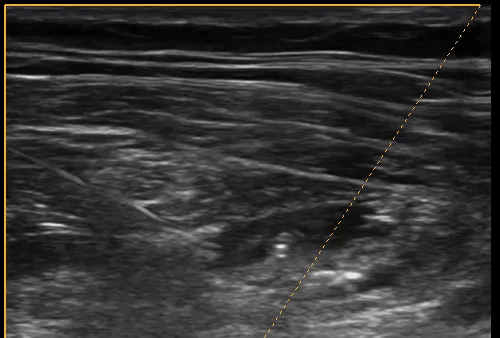

Clip 1- Right Inguinal Region (Left- Lateral, Right- Medial)

Image 1- Sono-Anatomy of the Performed Block

SONO-ANATOMY & TECHNIQUE

Infrainguinal fascia iliaca compartment - scanning approach

Place the probe over just under and parallel to the inguinal ligament in the lateral half. Slide the probe medially along the same plane along to identify the neurovascular bundle.

The femoral artery will be obvious as the most round and pulsating vessel and medial to this lies the femoral vein (remember NAVY). However, the femoral nerve is not often easily visualised yet until it has local anaesthetic around it and separated from the fascia and fat. Slide the probe slowly laterally and adjust by rocking until there is a clear demarcation of the sartorius muscle with fascia lata and iliaca on either side, with the iliopsoas muscle in the far field.

Insert the needle in-plane with the transducer. Inject the local anaesthetic just under the fascia Iliaca and observe the hydro-disection as shown. Note that this is NOT a femoral nerve block, but a compartment block- therefore the aim is to stay away from the nerve and administer the anaesthetic under the fascia iliaca which spreads along the compartment to block the main nerves innervating the hip (femoral, obturator and lat. cutaneous nerve of thigh). This requires adequate VOLUME for good coverage- hence using around 30-40ml total volume in most patients (you can dilute further with saline if more volume required).